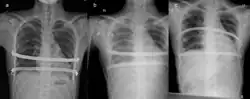

X-Ray of a 15-year-old male after undergoing the procedure